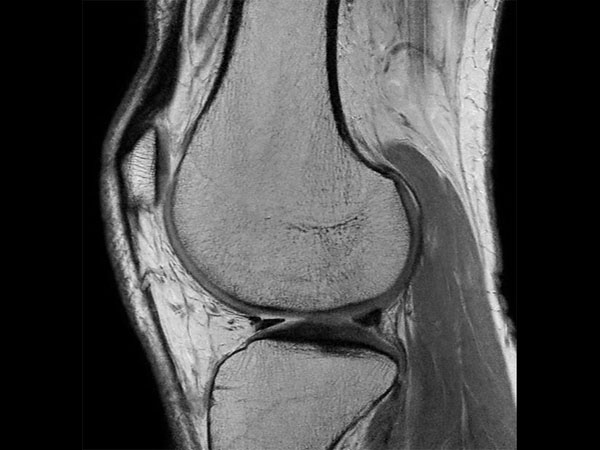

Middle aged board surfer presents with chronic knee pain. X-Ray shows no abnormalities. Follow-up MR examination requested.